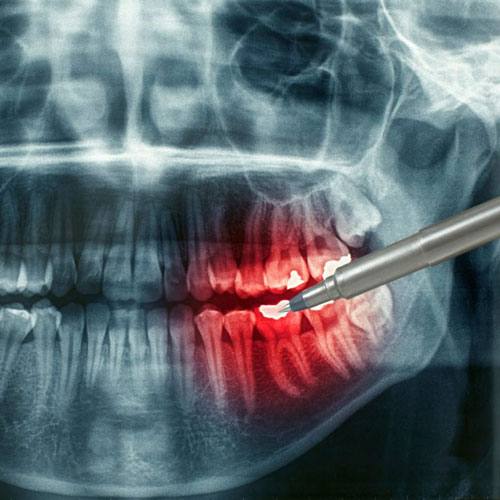

Our arsenal of dental examination techniques includes target intraoral X-ray imaging of teeth and panoramic tomography, as well as special-purpose dentofacial computer tomography.

A three-dimensional reconstruction procedure makes the diagnostics of the dentofacial area substantially more informative than regular X-ray imaging since the former enables studying of any area, at any angle, in any plane and at any section.

- Diagnostics of inflammatory changes of the bone tissue at the tooth root apex;

- Assessment of root canal sealing quality;